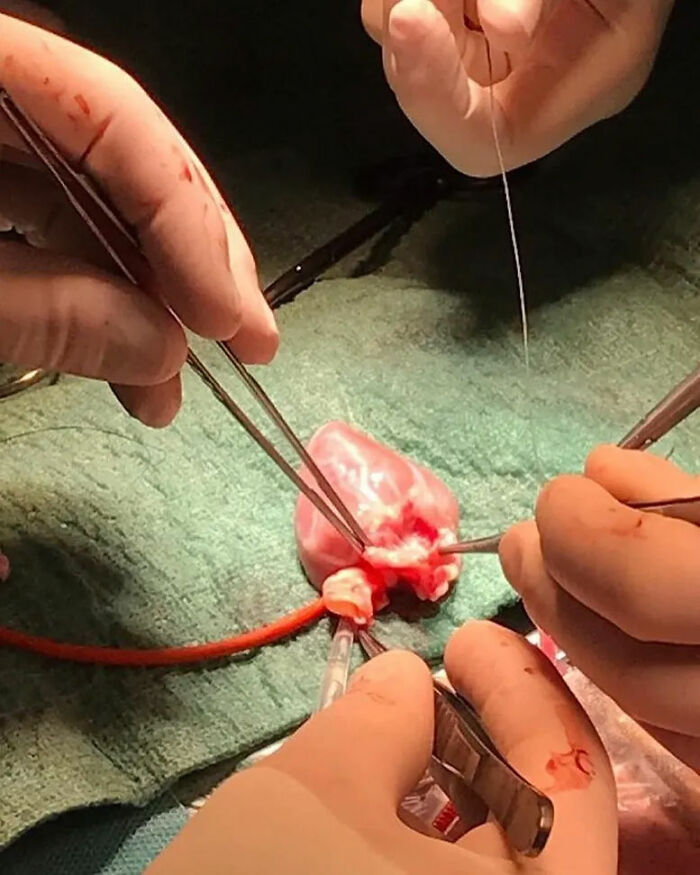

Pediatric Heart Transplantation

Heart Valve